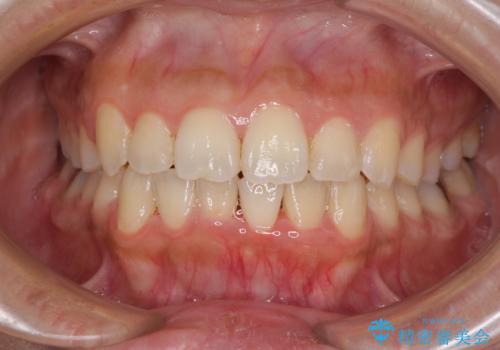

前歯のデコボコをインビザラインでスッキリと

- 上下前歯のデコボコを気にして来院された患者様です。

デコボコを解消する過程で、歯列の拡大により口元が突出する可能性があったため、4本の親知らずを抜歯しておき、歯列全体が後方に移動するように設計し、インビザラインにて矯正治療を行うこととしました。

日々の装着時間をしっかりと守って治療の臨んでくださったため、治療前のシミュレーションに近い形で矯正治療を進めて行くことができました。